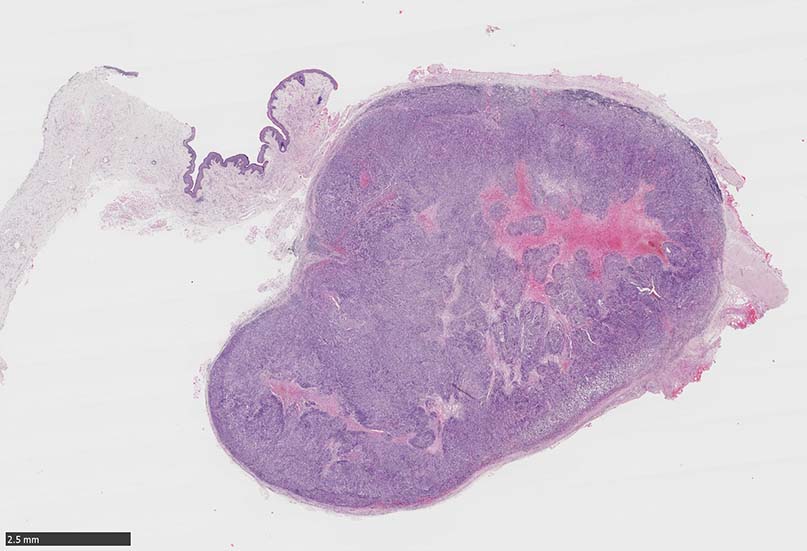

SPS244-Case01 右下眼瞼腫瘤 70歳代女性

再発腫瘤病変の組織像